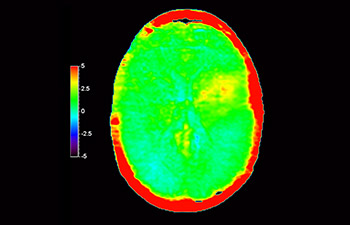

In een samenleving waarin veel neurologische aandoeningen voorkomen, streeft Philips naar een superieure duidelijkheid op het gebied van diagnoses en behandelingsbegeleiding voor alle patiënten. Hoewel MR vandaag de dag de gouden standaard is in neuro-oncologische beeldvorming, is er nog ruimte voor verbetering van de nauwkeurigheid bij het beoordelen van tumoren en follow-ups. 3D APT (Amide Proton Transfer) is een unieke, contrastvrije MR-beeldvormingsmethode voor de hersenen als antwoord op de vraag naar betrouwbaardere diagnostiek in de neuro-oncologie. 3D APT maakt gebruik van de aanwezigheid van endogene celeiwitten voor het produceren van een MR-signaal dat direct correleert met celproliferatie, een marker voor tumoractiviteit. 3D APT kan getrainde medische professionals ondersteunen bij het maken van onderscheid tussen laaggradige en hooggradige gliomen en tussen de ontwikkeling van de tumor en het effect van de behandeling1.

met 3D APT